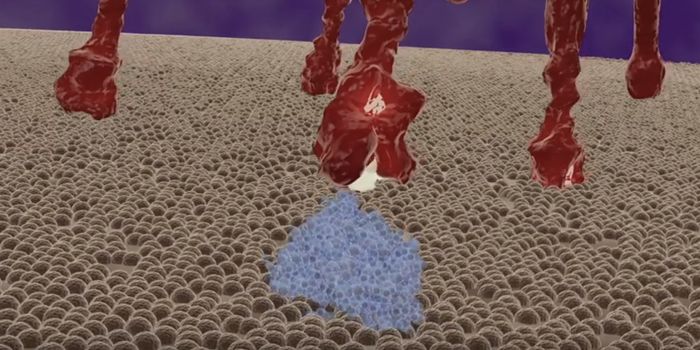

MAY 04, 2021Cell & Molecular BiologyYou can see the spike protein of the virus in action in this video.